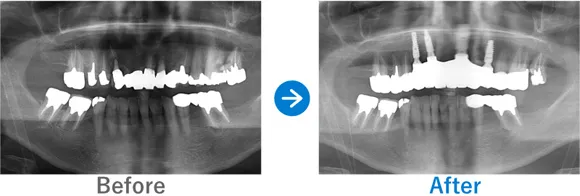

Case2

ブリッジで両隣の歯もダメに…。インプラント治療後は奥歯でしっかり噛めるように!

右下7はかなり前に抜歯後、ブリッジ治療済み。左下6は抜歯後、義歯を入れたがほとんど使っていない

インプラント4本:右下6・7、左下6・7

1,249,500円(内訳:GBR、インプラント4本(ネオデント)、ガイド、仮歯、セデーション、骨補填材、保証20年)

来院の背景

下顎の左右の臼歯部がブリッジによる影響で傷んでしまい、義歯に変更したもののほとんど使えない状態でした。奥歯で噛めないことにストレスを感じ、インプラントを検討。先にインプラント治療をしていた奥様からの紹介で来院されました。

治療結果

来院時の検査で、骨はやせてはいたものの治っている状態だったので、インプラント埋入と同時に骨補填をし、下顎の左右に2本ずつインプラントを埋入し治療完了しました。しっかり噛めるようになり患者様も喜んでおられます。今後はナイトガードを使用して、ブラキシズム(無意識下の歯ぎしり、食いしばりなど)の予防をしていく予定です。